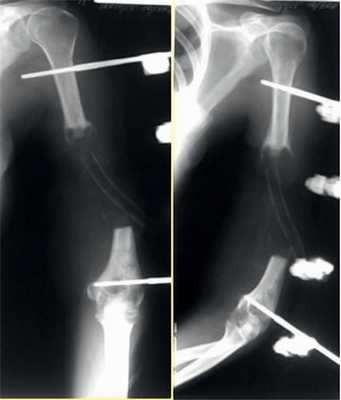

2. Больная В., 47 лет, поступила через 2 года после автотравмы с диагнозом: атрофический ложный сустав правой плечевой кости, перелом фиксатора (рис. 2). Рисунок 2. Рентгенограммы больной В., 47 лет (I), и функция конечности через 2 нед после операции (II). I: а - многооскольчатый перелом правой плечевой кости, б - интрамедуллярный остеосинтез, в - несостоятельность фиксатора через 3 мес, г - реостеосинтез пластиной с угловой стабильностью, д - перелом накостного фиксатора спустя 18 мес, е - реконструкция плечевой кости - накостный остеосинтез метафизарной пластиной с применением ротированного на сосудистой ножке надкостнично-кортикального аутотрансплантата, ж - консолидация ложного сустава через 5 мес; II - функция конечности через 2 нед после операции.